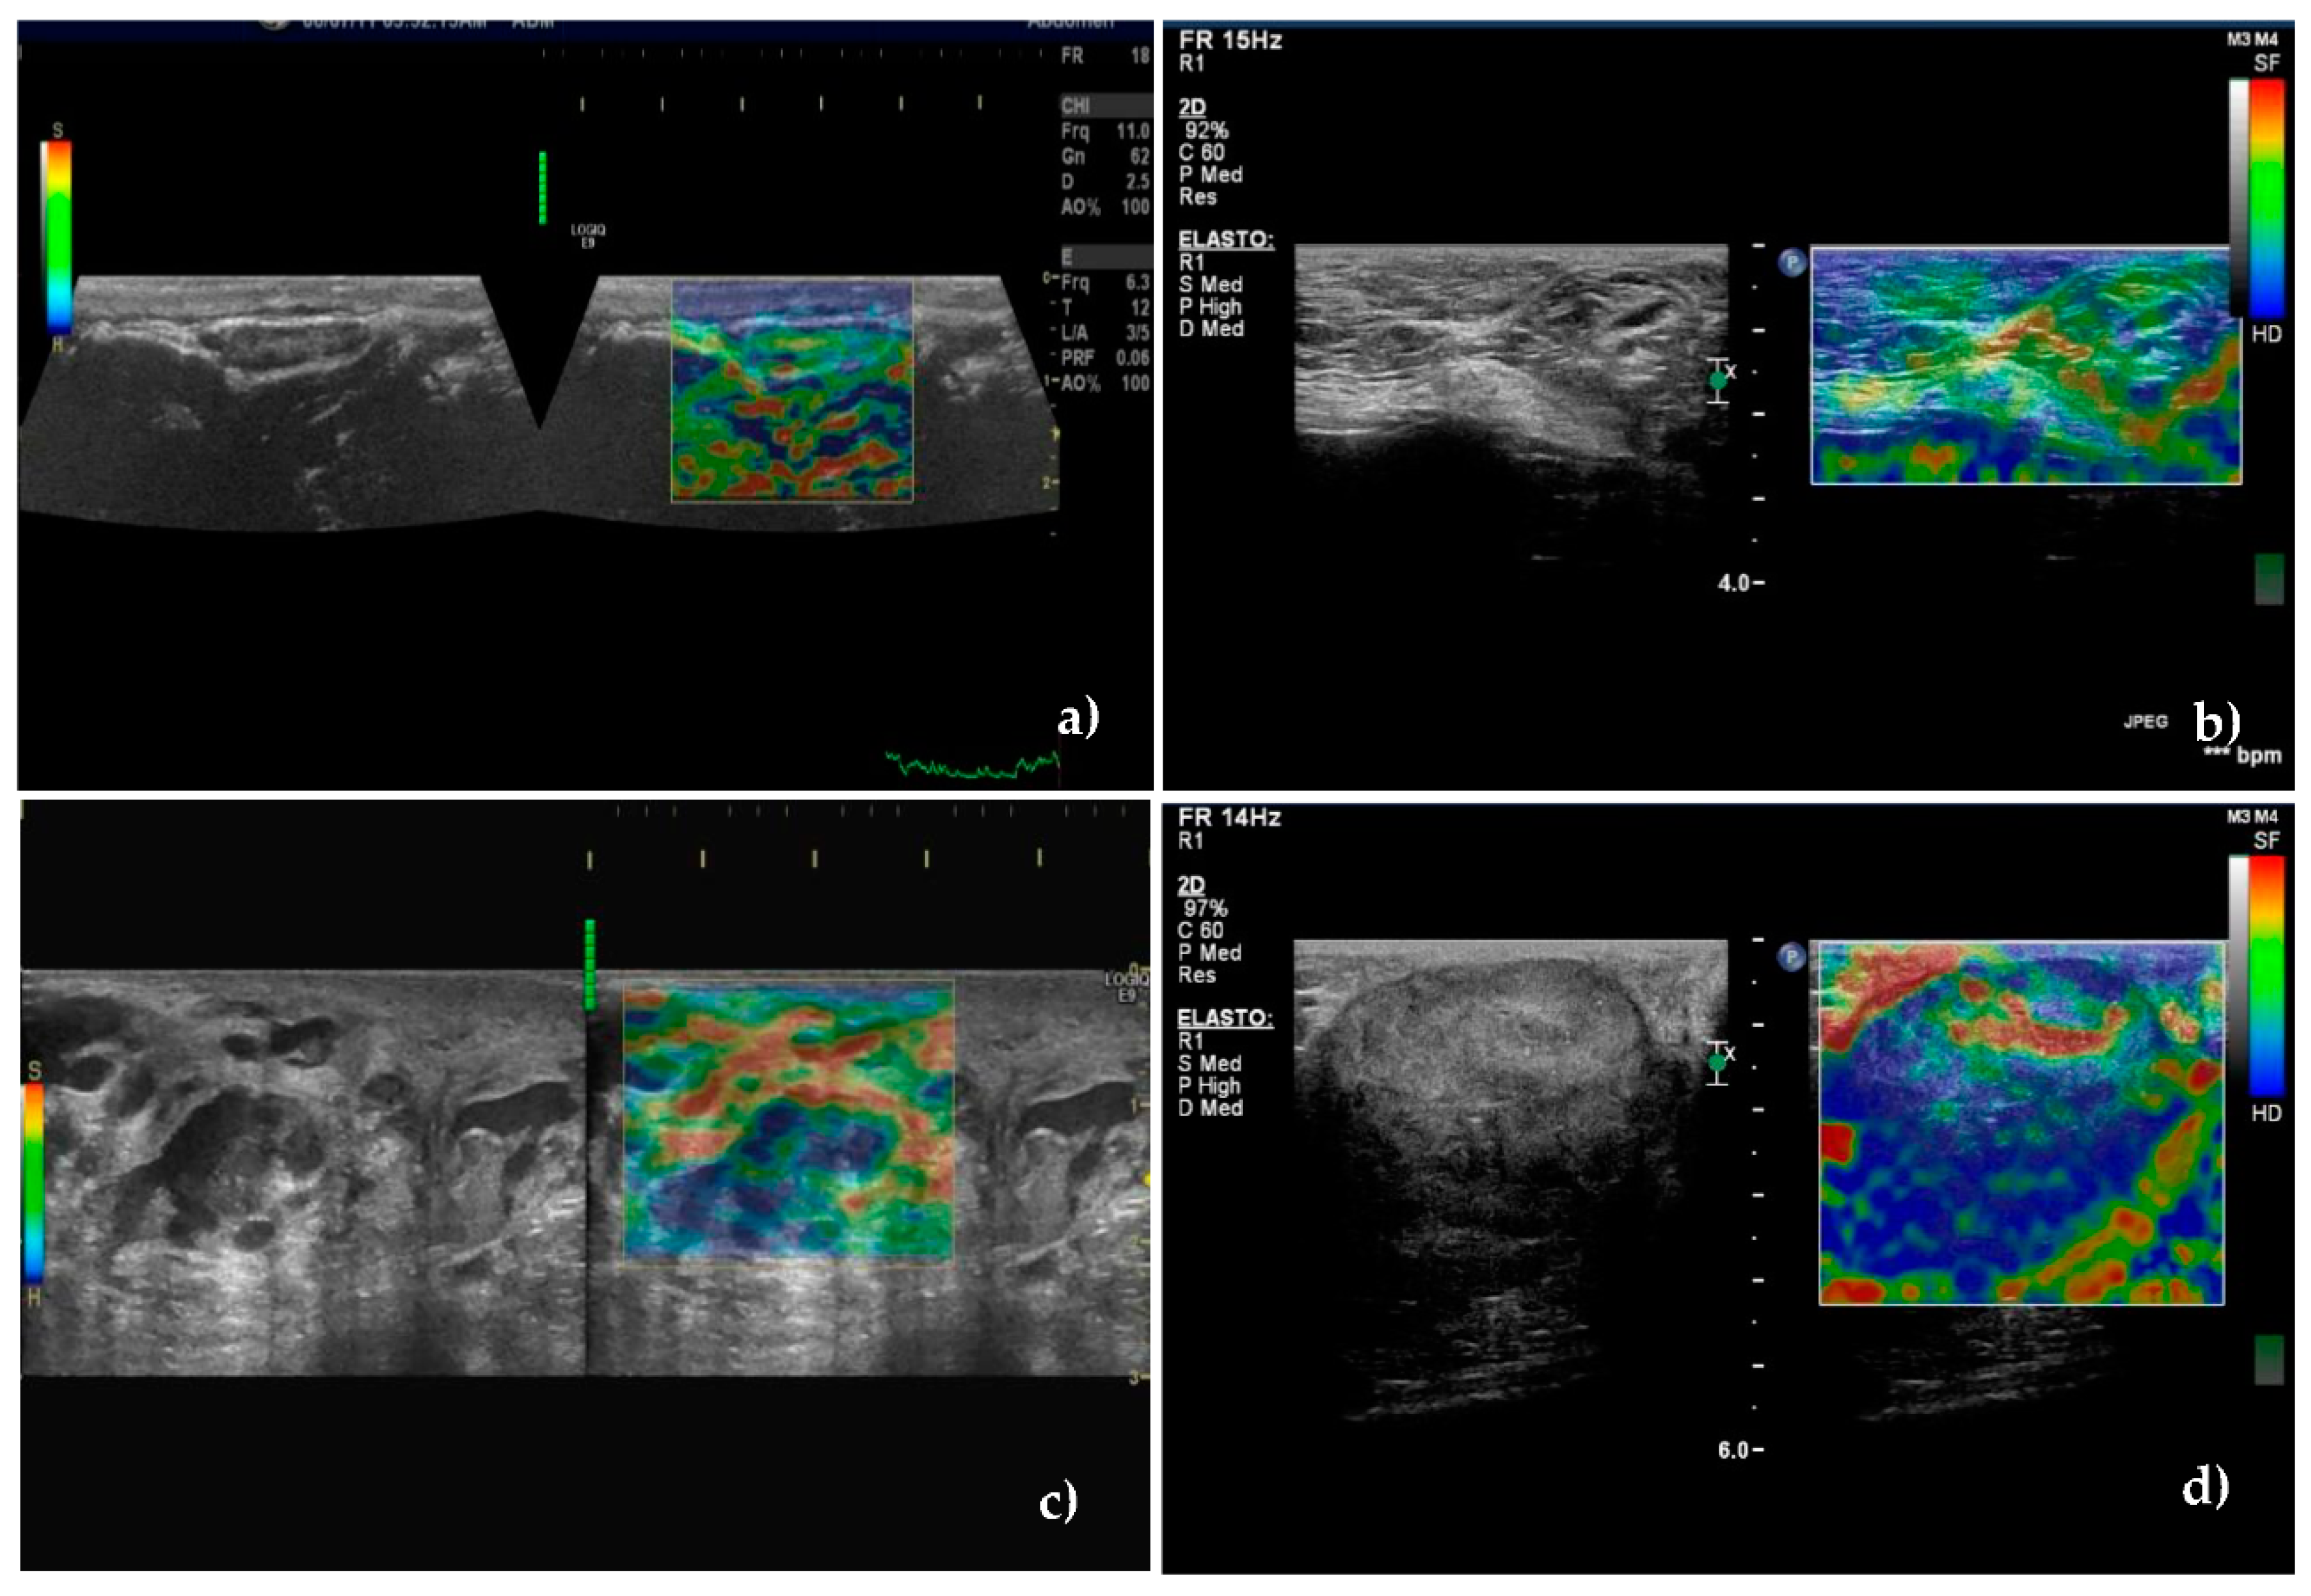

Using the score proposed by Alam et al. [49], which quantified the relative proportion of the areas with low deformability (or high rigidity), a cutoff value between scores 2 and 3 was established.

Among metastatic SLNs, 88.9% were classified in scores 3, 4, or 5 (hard). These scores were recorded in only 9.5% of the unaffected SLNs. Scores 1 and 2 were recorded in 90.5% of unaffected SLNs (Figure 5a,b) and in 11.1% of metastatic SLNs, (p < 0.001) (Figure 5c,d).

Figure 5. Sonoelastographic images of unaffected—(a,b)—and metastatic—(c,d)—sentinel lymph nodes. (a) Unaffected axillary sentinel lymph node showing soft appearance—total green with small blue areas corresponding to score of 1. (b) Moderately soft superficial inguinal sentinel lymph node with small scattered blue areas corresponding to score of 2. (c) Most of the superficial inguinal lymph node is blue with small green areas inside suggesting necrosis, corresponding to score of 4. (d) Hard-blue area occupying entire lymph node, with green rim corresponding to score of 5.

The classification of SLNs in a certain score is presented in Table 4. Stiffness was significantly higher in metastatic SLNs compared to the unaffected ones (Figure 5) having a very good SE, SP, PPV, NPV, and accuracy to identify the metastatic lymph nodes, of 88.9%, 90.5%, 89.69%, 86.36%, and 89.71%.